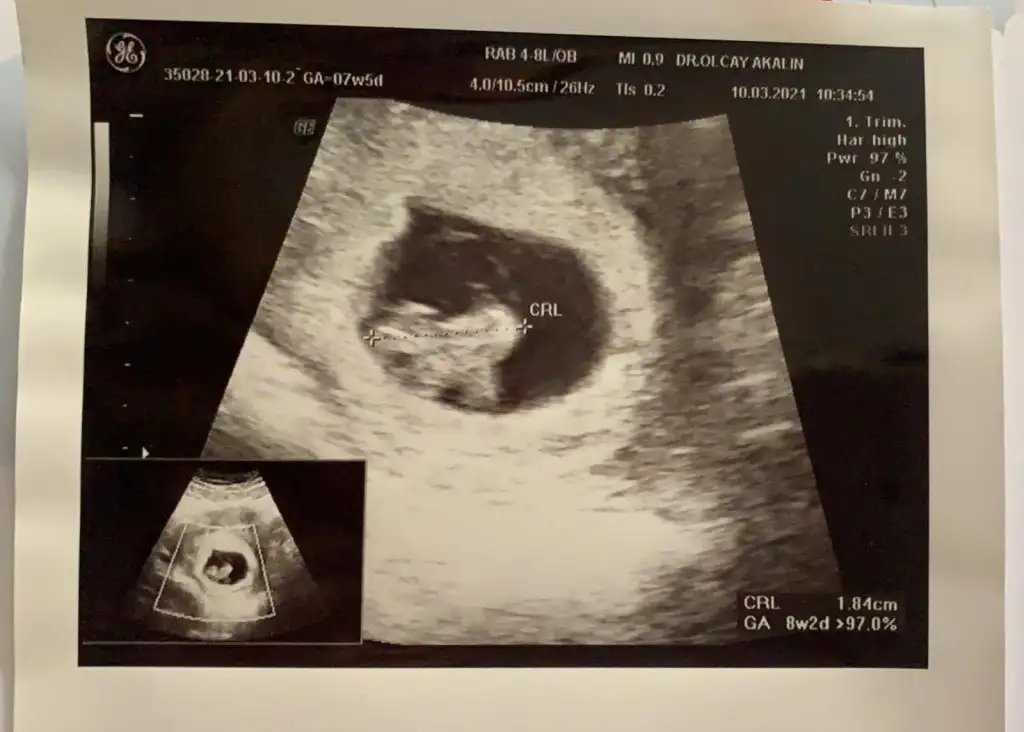

Merhaba 11+4de size usg atmıştım kız gibi demistiniz şimdi 14+5 atıyorum tekrar yorumlarmısiniz hala söylemedi doktorErkek görünüyor

Ay ben ikra kadar anlamam ama kız gibi geldi yaMerhaba 11+4de size usg atmıştım kız gibi demistiniz şimdi 14+5 atıyorum tekrar yorumlarmısiniz hala söylemedi doktor

11+4 de kız demiştim ama 14+5 de artık organı oluşmuş oluyor bakalım hayırlısı olsun tipi kız gibiMerhaba 11+4de size usg atmıştım kız gibi demistiniz şimdi 14+5 atıyorum tekrar yorumlarmısiniz hala söylemedi doktor

Teşekkür ederim doktorda ben kız diyorum ama emin değilim dedi netlesince yazicam size11+4 de kız demiştim ama 14+5 de artık organı oluşmuş oluyor bakalım hayırlısı olsun tipi kız gibi